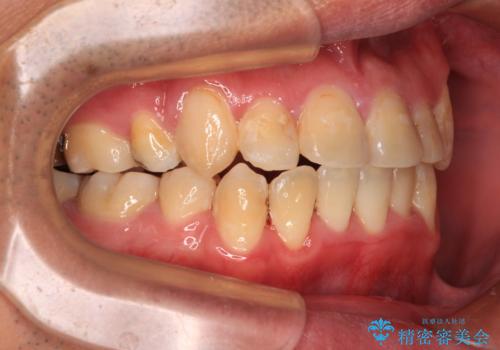

- 上下の八重歯やデコボコを気にして来院された患者様です。

上下ともに八重歯が顕著であったので、上下左右第一小臼歯4本を抜歯し、ワイヤー装置にて矯正治療を行うこととしました。

結婚式をきっかけに矯正治療を決意したとのことでしたが、挙式までの期間があまりにも短かったために、結婚式後に治療を開始することとなりました。

1年以上のゆとりを持って矯正治療を始める必要があります。